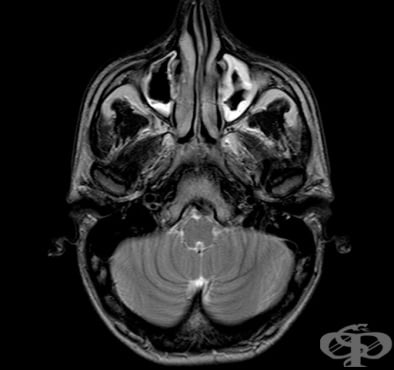

За поставяне на диагнозата остър синузит имат значение симптомите на пациента, лабораторните изследвания на кръвта, рентгенография на околоносните синуси, при необходимост и компютърна томография. При хроничен синузит е добре да се направи и микробиологично изследване. Болният трябва да отиде на л...

Синузит Възпалени синуси Синузит Симптоми при синузит Синузит Синузит Риноскопия Рентгенография максиларен синузит Компютърна томография етмоидакен синузит ЯМР синузит Одонтогенен синузит Лечение на синузит

СинузитВъзпалени синусиСинузитСимптоми при синузитСинузитСинузитРиноскопияРентгенография максиларен синузитКомпютърна томография етмоидакен синузитЯМР синузитОдонтогенен синузитЛечение на синузитЛечение на синузит